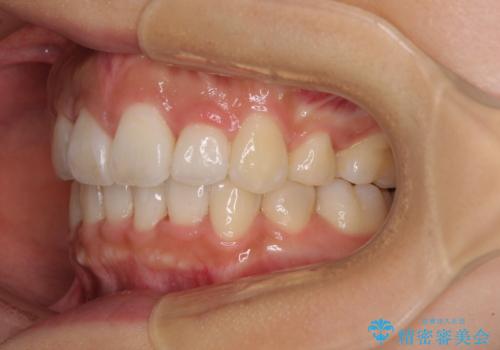

スッキリとした口元へ 出っ歯の抜歯矯正

- 上下の出っ歯を気にして来院された患者様です。

口元を積極的に引っ込めるために、上下左右の第一小臼歯を4本抜歯することとしました。

最終的には上下の正中も合い、横顔の印象が変わるほどスッキリとした口元となりました。